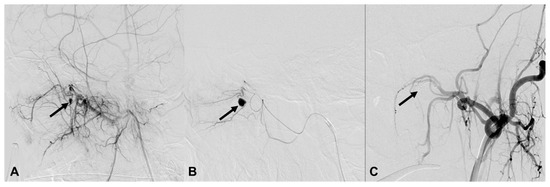

| 3 | 46/M | Fall | Epistaxis and oral bleeding | Le fort II fracture | EV, L IMA branch | Coil | Stable 260 d F/U |

| 4 | 57/M | Fall | Bleeding | Facial and sphenoid bone fracture | EV, L IMA branch | Particle | Stable 4 d F/U |

| 5 | 39/M | Fall | Epistaxis | Facial and sphenoid bone fracture | EV, R IMA branch EV, R cavernous ICA (CCF) | Coil, particle | Stable 39 d F/U |

| 7 | 62/M | TA | Epistaxis | Organizing hematoma, L maxillary sinus | EV, L IMA branch | Coil, glue | Death 911 d d/t esophageal cancer |

| 8 | 80/F | TA | Massive oral bleeding | Le fort II fracture | EV, L IMA branch EV, both facial | Particle, coil | Stable 651 d F/U |

| 9 | 61/M | TA | Epistaxis | Le fort II fracture | EV, L IMA branch | Coil | Stable 548 d F/U |

| 11 | 64/M | Blunt | Epistaxis and oral bleeding | Le fort II fracture | EV, R IMA branch | Coil | Transferred and lost F/U |